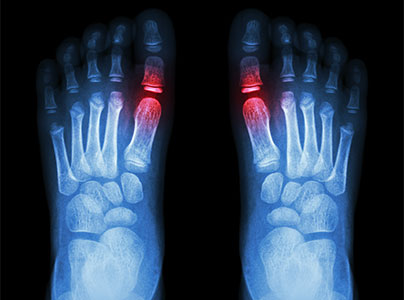

Gout

Gout is a metabolic disease involving sharp crystals of uric acid (urate) forming in joints or other areas of the body. Gouty attacks come on episodically, causing joint swelling and pain. Pseudogout is a similar condition which involves calcium pyrophosphate crystals.

Gout can affect both women and men but is much more common in men and overall affects approximately 4% of the U.S. population.1 Signs and symptoms of a gouty attack may include:

• Severe and sudden pain in joint(s) (even light touch is painful)

• Commonly involves joint at base of big toe

• Arthritis pain comes on within hours and may last for several days

• Involved joints may be warm, red, and swollen (also present with infections)